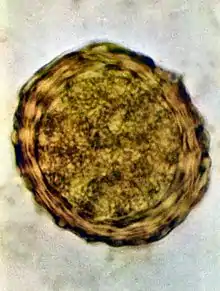

Ovos

Os ovos tem a princípio cor branca, mas devido ao contato com os pigmentos biliares das fezes, adquirem um tom castanho, às vezes descrito como de amarelo-escuro a marrom.[4] Tem formato oval a redondo e medem 45 a 75 micrômetros (μm) de comprimento e 35 a 45 (ou 50, a depender da fonte)[5] μm de largura;[6] possuem uma cápsula espessa graças a membrana externa mamilonada, formada por mucopolissacarídeos e secretada pela parede uterina. Internamente a esta membrana, existe outra constituída de quitina e proteína. A mais interna é delgada e impermeável à água constituída de 25% de proteínas e 75% de lipídios. É a camada mais interna que garante ao ovo a capacidade de resistir às condições adversas do ambiente. Em seu interior, os ovos tem uma massa de células germinativas. É possível encontrar nas fezes humanas ovos inférteis de áscaris, isso ocorre quando a fêmea do verme não foi inseminada, ou quando está iniciando a oviposição.[5] Pode-se identificar ao microscópio esse tipo de ovo pois eles possuem o interior desorganizado, com citoplasma granuloso e sem estruturas visíveis.[4][6] A membrana mamilonada é mais delgada e são mais alongados que os ovos férteis, medindo 80 a 90 μm de comprimento. Algumas vezes, mesmo os ovos férteis podem não ter a membrana mamilonada, sendo chamados de ovos decorticados.[4]